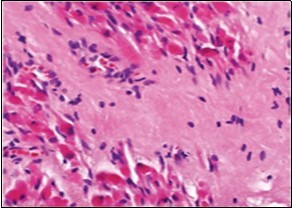

On microscopy, a collagen- rich, minimally cellular, fibrotic soft tissue nodule is exemplified which simulates a scar or conventional fibroma. The neoplasm is comprised of uniform, plump, fibroblastic or myo-fibroblastic cells encompassed in a collagen-rich stroma with infiltration and entrapment of skeletal myocytes 5, 6. Cogent histological examination depicts replacement of muscle fibres and muscle mass with fascicles of fibrous tissue comprised of mature fibroblastic cells, thereby conferring fibrosis 6. Figure 1, Figure 2, Figure 3, Figure 4, Figure 5, Figure 6, Figure 7, Figure 8.

Figure 3.Fibromatosis colli depicting fascicles of fibroblasts and myo-fibroblasts admixed with a collagenous stroma and extravasation of numerous red blood cells 10.